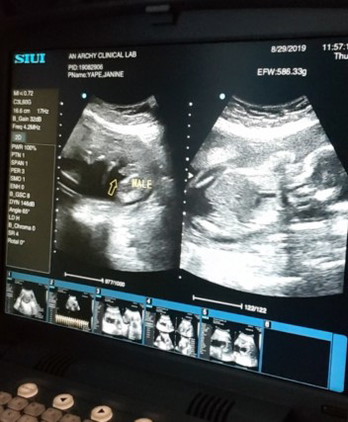

Baby Boy! ?

Mga mommies..medyo worried po kc ako sa baby ko kc nung pagtungtong nya nung 4 months sobrang active sya sakin at ramdam n ramdam ko bawat pagpitik nya sa tummy ko..kaso po nung pagtungtong ng 5 months nd ko na po sya ramdam s tummy ko wla n pong pagpitik pitik manlang..kya sobra na po akong nagwoworied kung ok lng ang baby ko kung ok p po heartbeat nya..kya nag decide na ako magpa ultrasound pra malaman..bali kakapa ultrasound ko lang po knina..thanks god ? ok po ang heartbeat ni baby ko..? 150bpm ? at nalaman ko ndin gender nya..? ang tanong ko po pag baby boy po ba hindi tlga sya magalaw sa tummy? Tas pag girl medyo malikot? Boy po gender ni baby..nd sya magalaw kc sakin eh..thankyou po..? #22weeksand4dayspreggy ?❤